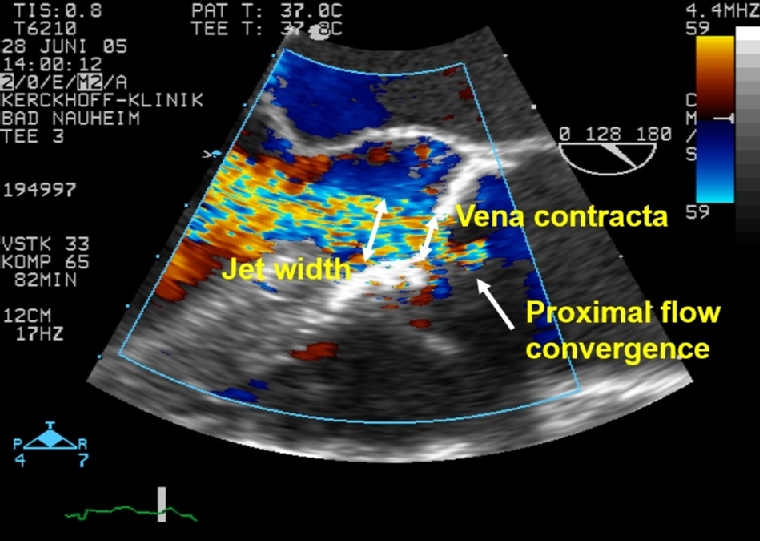

Trivial valvular regurgitation is considered physiological except for the AV. Similar to MR, AR is quantified on a three-grade scale. Colour Doppler echocardiography is the primary method for assessment of AR. While the apical approach is most sensitive for detection, the zoomed parasternal long- and short-axis views are essential for semiquantitative characterisation with visualisation of the three components of the colour jet - proximal flow convergence, vena contracta (VC) and jet width (Figure 1). The jet width and area relative to the left ventricular outflow tract (LVOT) dimension measured within 1 cm apical to the aortic valve leaflets (Figure 2) are an elementary measure of AR severity, but not reliable in eccentric or multiple jets. The VC is the narrowest portion of the regurgitant jet that occurs at or immediately downstream to the regurgitant orifice and reflective of the effective regurgitant orifice area (EROA). The VC width is a simple, easy to obtain semiquantitative parameter that represents a surrogate measurement of the regurgitant orifice area. Since the width of the VC is small, even little measurement variability may have a decisive impact on AR grading. In contrast to MR (VC 7 mm), the cut-off value for severe AR is smaller (6 mm), taking into account the longer duration of diastolic AR compared to systolic MR at rest resulting in a comparable regurgitant volume (RV). Importantly, the length and area of the AR jet into the LV is not a reliable parameter of AR severity. Quantitative methods include pulsed wave Doppler, volumetric and proximal isovelocity surface area (PISA) measurements allowing calculation of the EROA, absolute RV and regurgitant fraction (ratio of RV to forward stroke volume) [17,18]. EROA and RV provide the strongest imaging predictors of outcome in AR [19].

216_Brandt_Figure_1_Chronic aortic regurgitation diagnosis and therapy in the modern era.jpg